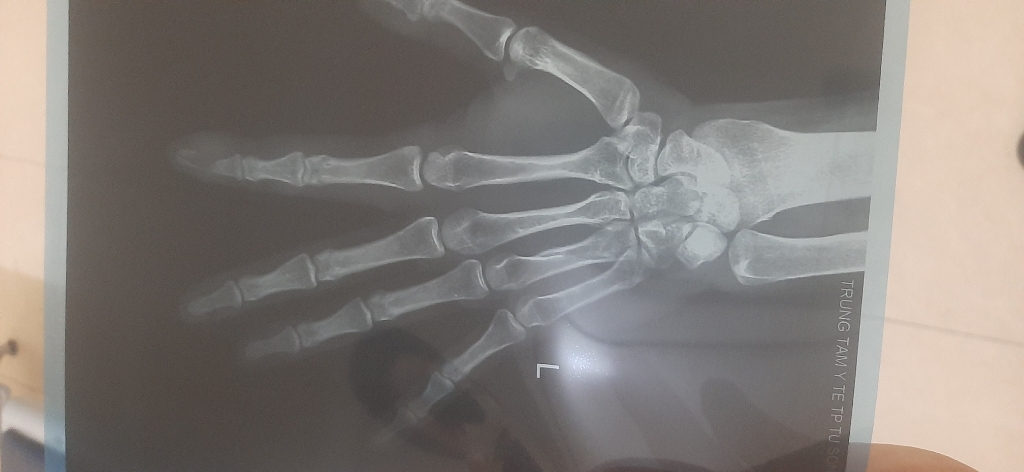

Em bị máy kẹp gãy rời đốt 3 .ngón 2 bàn tay trái.từ 20/11 giờ không khỏi và hoại tử chết da.khám ở địa phương các bác sỹ bảo tháo đốt gãy.nhưng em muốn bảo tồn.mong bác sỹ tư vấn ạ. Xin Cảm ơn